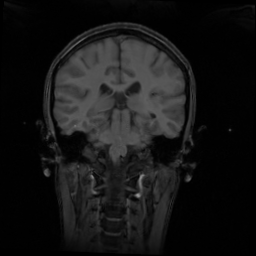

Figure 9: Examples of 3D volumes of average errors for the normal IBSR and LPBA40 datasets, as well as for the pathological BRATS and TBI datasets. For IBSR/BRATS, we show results for BEaST*. Images and their brain masks are first affinely aligned to the atlas. At each location we then calculate the proportion of segmentation errors among all the segmented cases of a dataset (both over- and under-segmentation errors). Lower values are better (a value of 0 indicates perfect results over all images) and higher values indicate poorer performance (a value of 1 indicates failure on all cases). Clearly, BSE and CNN struggle with the BRATS dataset whereas our PCA method shows good performance across all datasets.